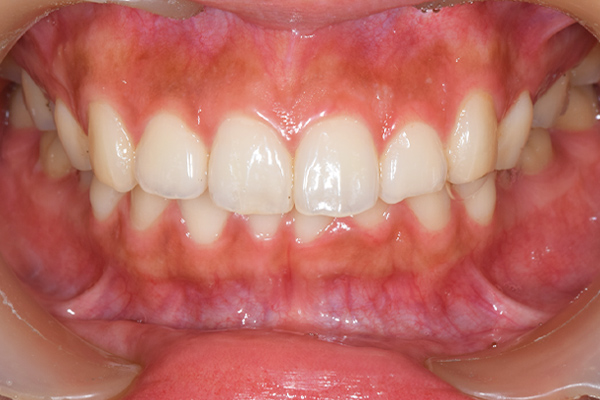

歯列矯正・インレー・クラウン症例

前歯が黒っぽいのが気になる、

悪いところは全部治したい

年齢 54代女性

主訴 歯をきれいにしたい

治療

期間

4年

費用 セラミックインレー 12本

660,000円

オールセラミックプレミアムクラウン 3本

495,000円

矯正 874,900円

計 2,029,900円(税込)

症例写真(治療後)

担当医師所見

矯正装置をつけています。だんだん八重歯が動いてきているのがわかります。今回のケースでは、抜歯を行わずに矯正ができました。

治療後:

矯正治療と虫歯の治療すべて終わったときの写真になります。見た目も最初の頃とは全く違いますし、お口の中もすごく綺麗です。

方針

まずは虫歯の治療を行い、被せ物をする部分は仮歯をいれて矯正を行う。矯正終了後、仮歯の部分を最終的な被せ物に変えていく。また気になっていた銀歯もセラミックに変えて終了となった。

内容

セラミックインレー、オールセラミックプレミアム、矯正